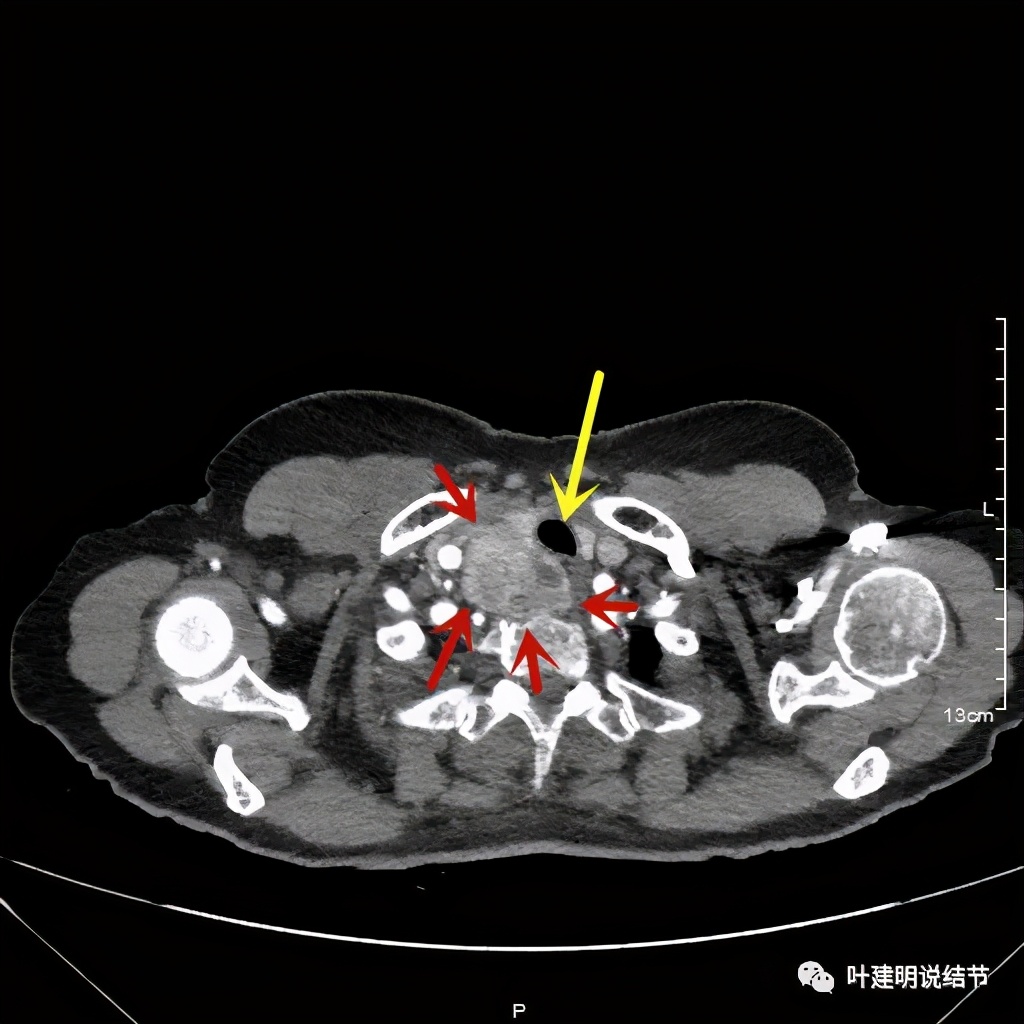

胸顶就开始有肿瘤了,黄色示受压迫移位的气管,红色示肿瘤

上图红色示肿瘤,黄色示气管,粉色示肿瘤与气管关系密切,而且肿瘤密度不均杂乱